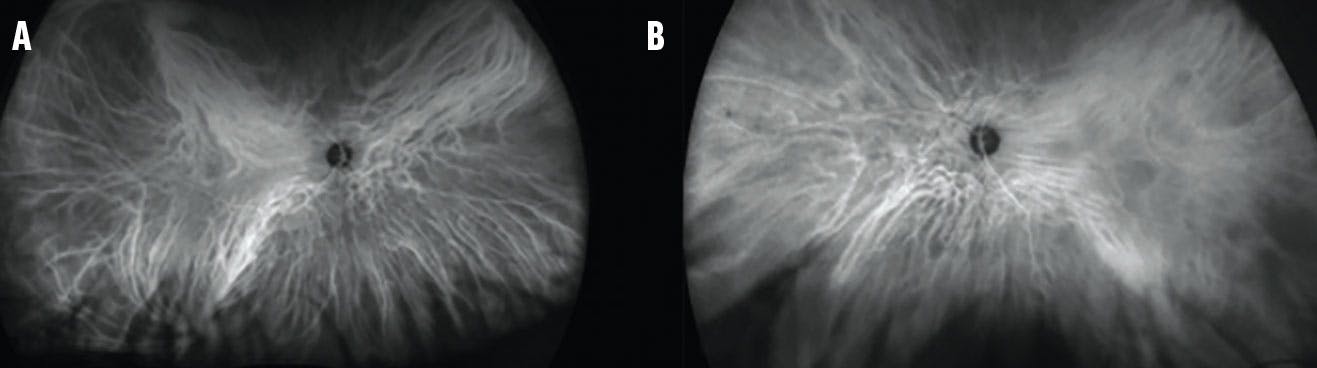

<p>Figure 2. Fundus autofluorescence of the right (A) and left (B) eye showed linear hyperreflective streaks compatible with the pattern noted on fundus photography.</p>

Figure 2. Fundus autofluorescence of the right (A) and left (B) eye showed linear hyperreflective streaks compatible with the pattern noted on fundus photography.

OCT revealed characteristic undulations of the RPE consistent with choroidal folds (Figure 3). Fluorescein angiography (FA) highlighted the choroidal folds in each eye (Figure 4). ICG did not reveal any choroidal masses (Figure 5), and a CT of the orbit was within normal limits. Blood workup was unremarkable.